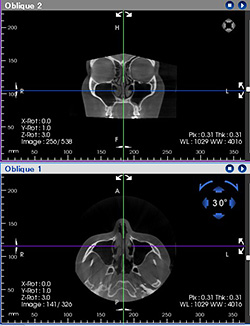

CT撮影

上顎洞と鼻腔の狭いところに根の先が入り込んでおり、表裏が逆になっているのがわかります。

犬歯だけを中心に描出し長さを測ります。現在この犬歯を引っ張り出し矯正治療中。